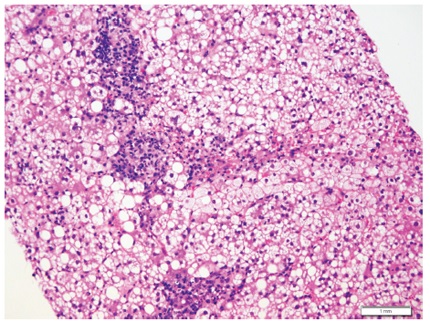

La esteatosis es la acumulación de grasa, hallazgo comúnmente observado en las biopsias. Un algoritmo útil para orientar el diagnóstico, es observar la presencia o no de células balonizadas y cuerpos de Mallory-Denk (figura 9). Este tema se trató extensamente en un artículo anterior (28).

En la figura 10 se presenta el algoritmo utilizado para este patrón.